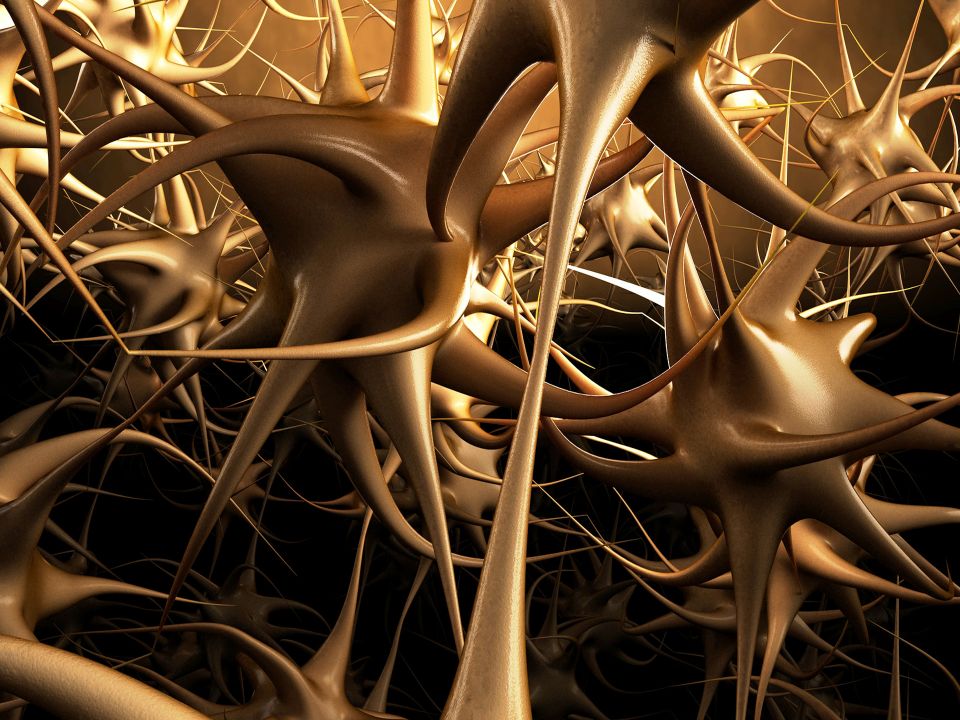

Pain pathways:

The mechanisms enabling us to sense pain are complex. What you feel depends on many factors, including how active you are and whether or not you are already feeling stressed.

Skin receptors report a painful stimulus by sending electrical messages along sensory nerve fibers to the spinal cord. From there they travel to the brain, where the signals are interpreted as the sensation of pain. Sometimes you can feel pain in one part of the body even though the area affected is actually elsewhere. This is called referred pain, and one example is angina pain originating from oxygen starvation of the heart muscle but felt in the upper arm, shoulder and neck.

At times of acute stress, the brain produces chemicals called endorphins. These reduce the perception of pain by blocking the action of the chemical messengers that transmit pain signals between nerve cells.

Pain may be partly or completely blocked by a process known as ‘gate control’. Nerve messages carrying information from the skin about other sensations can sometimes bar the transmission of pain messages. This happens when nerve fibers that are carrying ‘non pain’ messages prevent nerve fibers that are carrying pain messages from relaying these signals up the spinal cord. It explains why therapies involving touch, pressure, heat and cold can relieve pain.